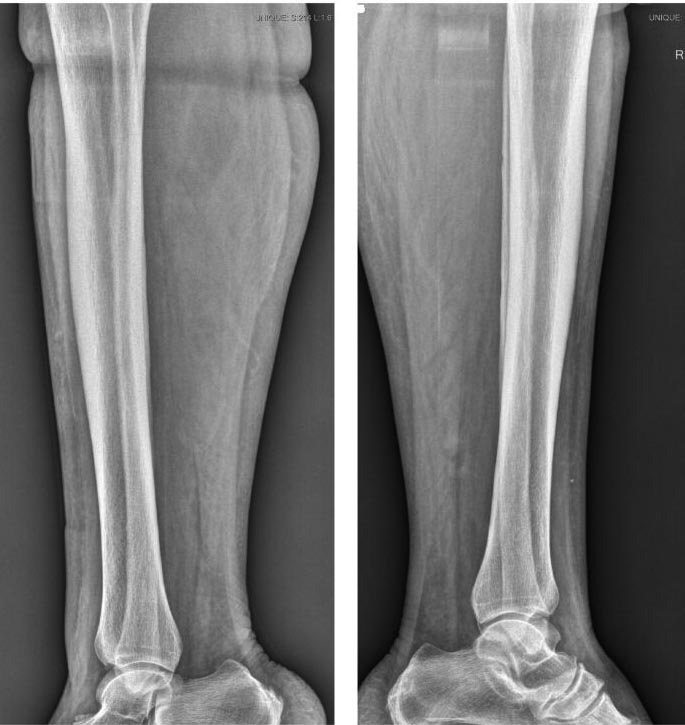

Рентген

Боковой снимок

А какая голень правая или левая? На Р грамме правой голени в боковой проекции какое то инородное тело в мягких тканях на границе с/3-н/3 или артефакт?

Левая нога течет. Я тоже обратил внимание на этот артефакт. Но в костях как на первом снимке так и на этом одинаково все.

А почему сразу кость?!))..кость вродь нипричём.Та и при любом раскладе,хоть ХВН, СД, или инородное тело необходимо сначала очистить рану(хирургически или консервативно(трипсинчиком)),а потом вторично заживлять.Да,можно рискнуть иссечь в пределах здоровых тканей и наложить швы,но маловероятно т.к. можно получить рану ещё больших размеров.Можно ещё добавить пентоксифиллин,актовегин,метилурацил и т.д.Но на правом снимке мне тож не нравиться вон та белая точка.

Может быть что угодно, включая опухоль. Снимки когда сделаны? Может быть, свежие сделать и сравнить?

Первый снимок сделан при получении травмы, его нет на руках, но я точно помню там без проблем, а тот который я выложил неделю назад